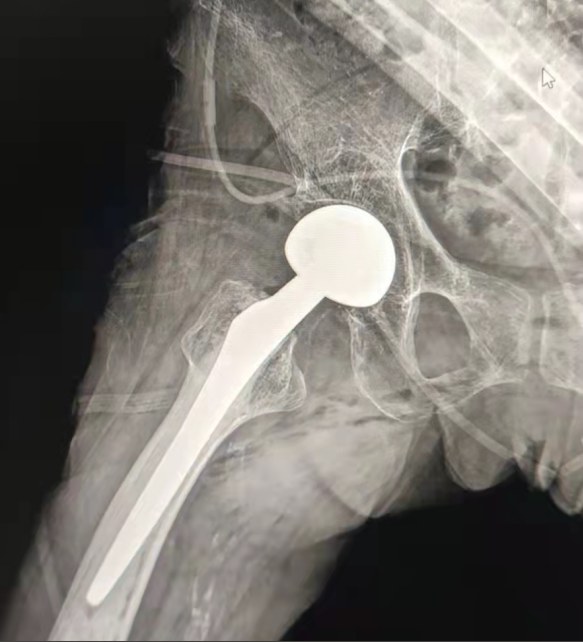

Vaka paylaşımı | 70 yaşında bir hasta, lepu çimentolu kalça sistemi ile toplam kalça değiştirme aldı

Çimentolu kalça sistemi:

Co-cr-mo alaşımlı malzemeler

Yüksek aşınma direnci

Büyük mekanik mukavemet

Omuz ipliği tasarımı

12/14 standart konik tasarım